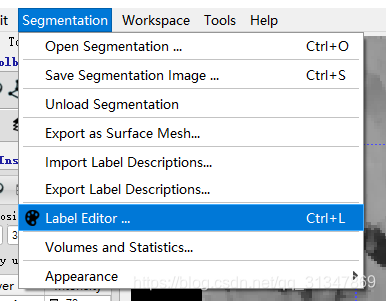

修改 label:Segmentation -> Label Editor...

在 Description 处可修改当前 label 的名称,在 color 处可修改 label 的颜色,点击 New 可以新建 label,Opacity(不透明度):在 3D 分割中,如果有一个结构阻挡了分割的结构,可以使标签变得部分透明 ,Visibility:隐藏标签